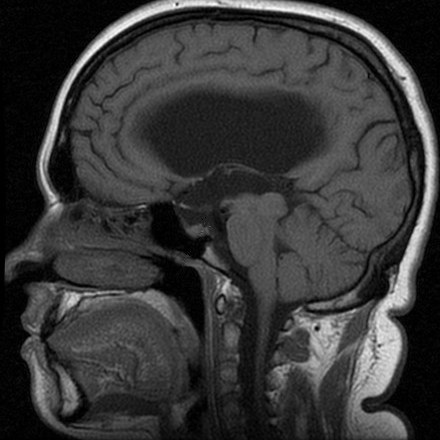

Внутричерепная гипотензия: КТ-исследования и их интерпретация

Раздел: Образы вокруг